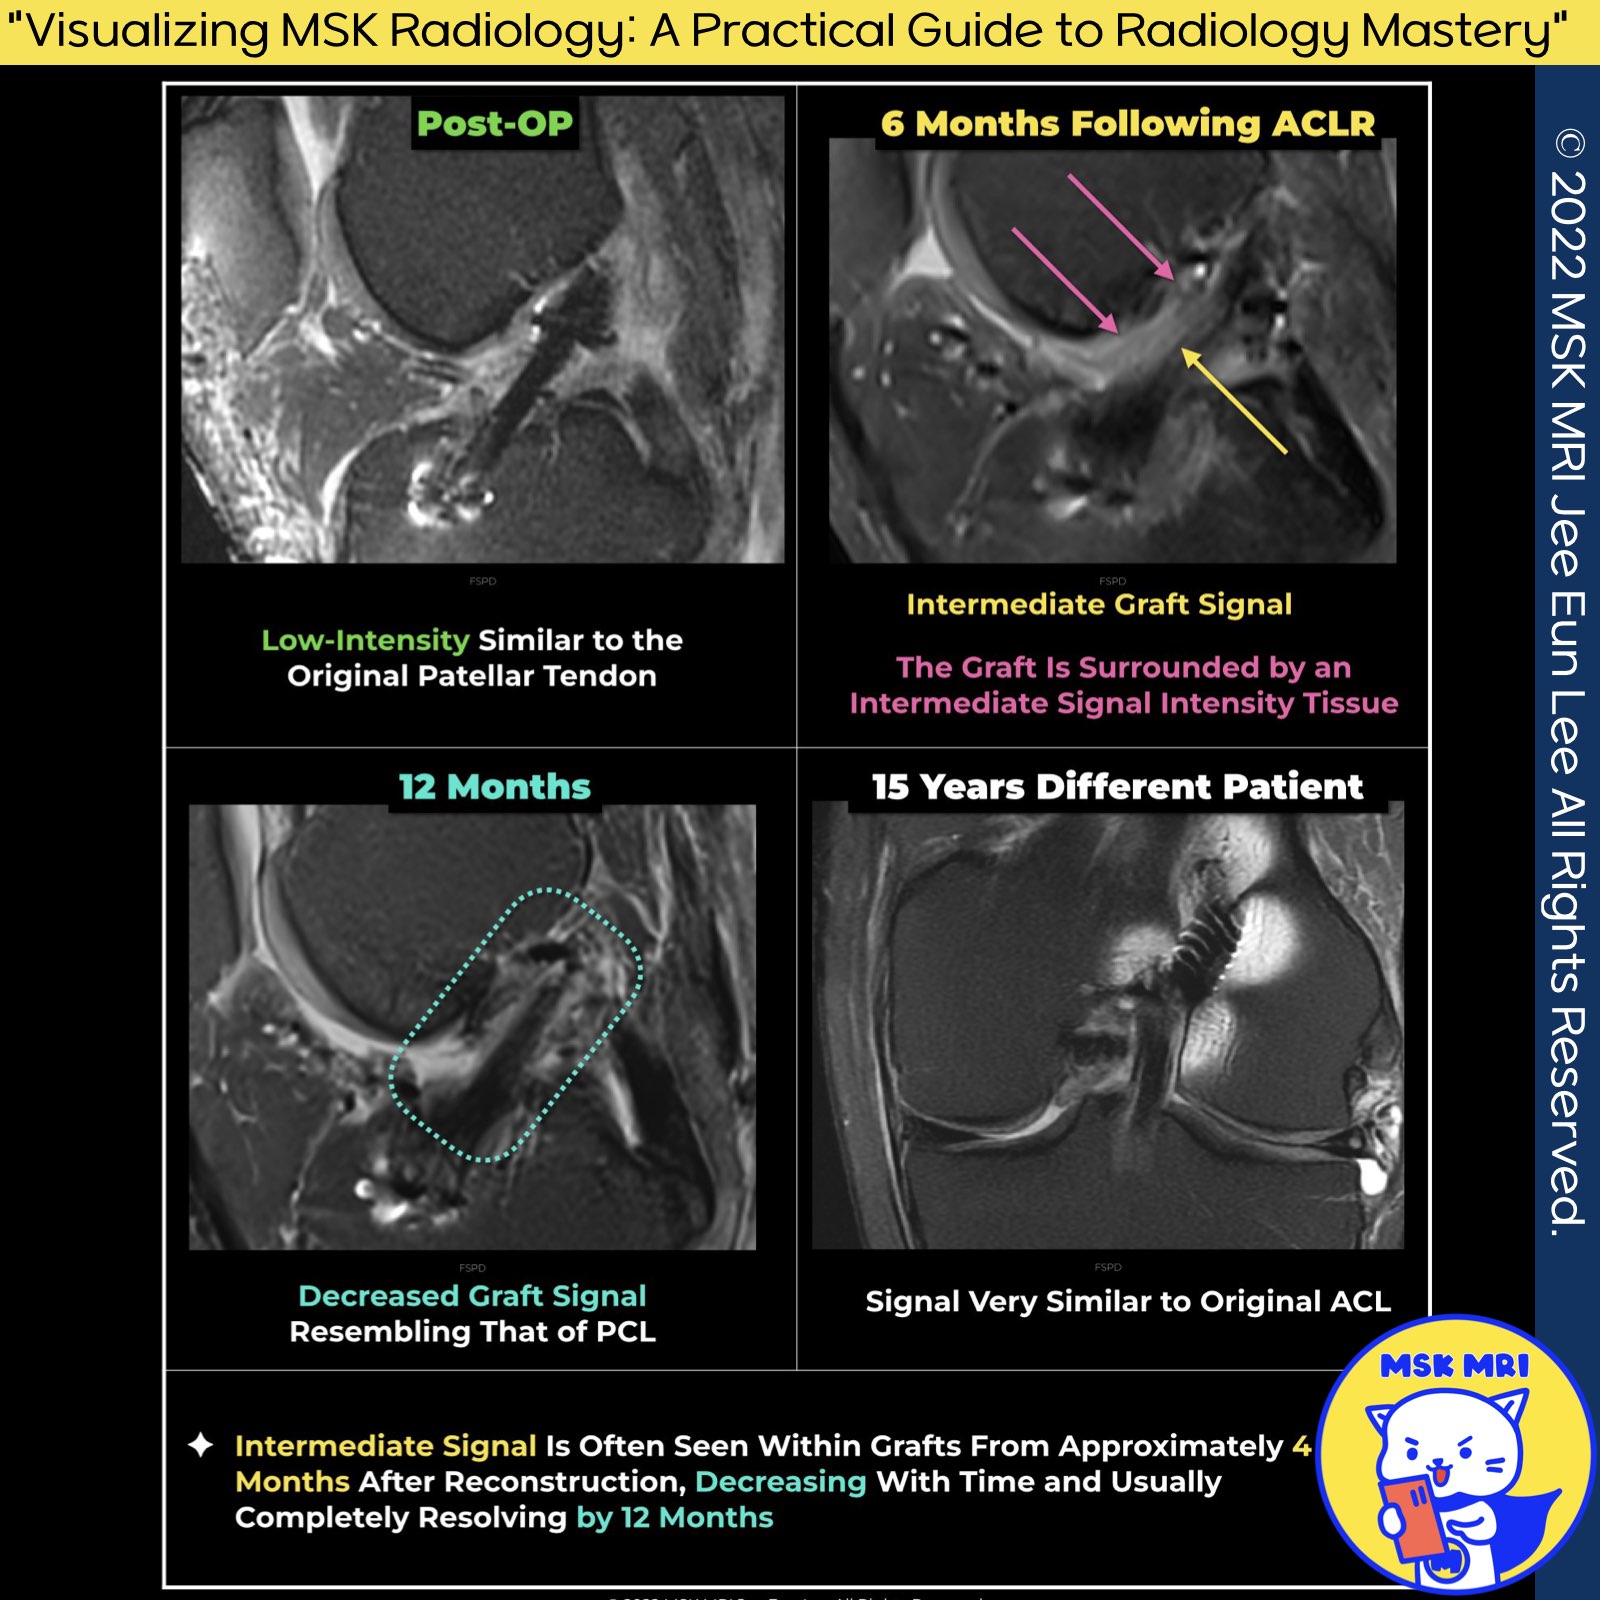

MR Postoperative Appearance of Reconstructed ACL

1️⃣ Initial Imaging After Surgery:

- The graft typically exhibits low to intermediate signal intensity due to its avascular nature.

2️⃣ Intermediate Stage (4 to 8 Months After Reconstruction):

- Within this timeframe, intermediate signal intensity is often observed within grafts.

- This signal intensity decreases over time and usually resolves completely by 12 months post-surgery.

- The increased signal is attributed to graft revascularization and synovialization processes.

📌Tendon Graft "Ligamentization" Process:

- Following anterior cruciate ligament reconstruction (ACLR), the tendon graft undergoes "ligamentization."

- Reported lengths of this process vary from 6 to 48 months.